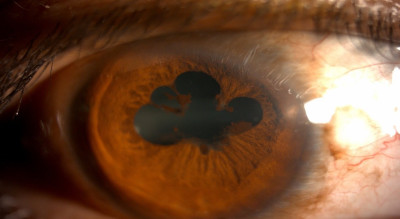

मोतीबिंदू म्हणजे डोळयाच्या बाहुलीतले भिंग नेहमीप्रमाणे काचेसारखे पारदर्शक न राहता तांदळाच्या दाण्यासारखे पांढुरके होते. यामुळे प्रकाशकिरण आत शिरायला अडथळा होतो. मोतीबिंदू सहसा उतारवयात येतो. मधुमेहात तो लवकर येऊ शकतो.

मोतीबिंदू आल्यावर नेहमीची तक्रार म्हणजे अंधुक दिसणे. रात्री गाडी चालवतांना समोरचा लाईट जास्त त्रासदायक होतो. दिव्याभोवती रंगीत कडी दिसतात. डोळयांसमोर काळे वर्तुळ दिसते. दिवसा (जास्त प्रकाशात) कमी दिसते. पण संध्याकाळी (कमी प्रकाश असतो तेव्हा) दिसण्यात थोडी सुधारणा होते, एकाऐवजी अनेक प्रतिमा दिसणे हे पण एक लक्षण आहे. कालपरत्वे दूरच्या आणि जवळच्याही वस्तू दिसणं बंद होतं. म्हणजेच मोतिबिंदू पिकतो. जास्त पिकल्यास काचबिंदूही होऊ शकतो. मोतीबिंदू किती पिकला आहे यावर तक्रारींचे स्वरूप अवलंबून असते इत्यादी.